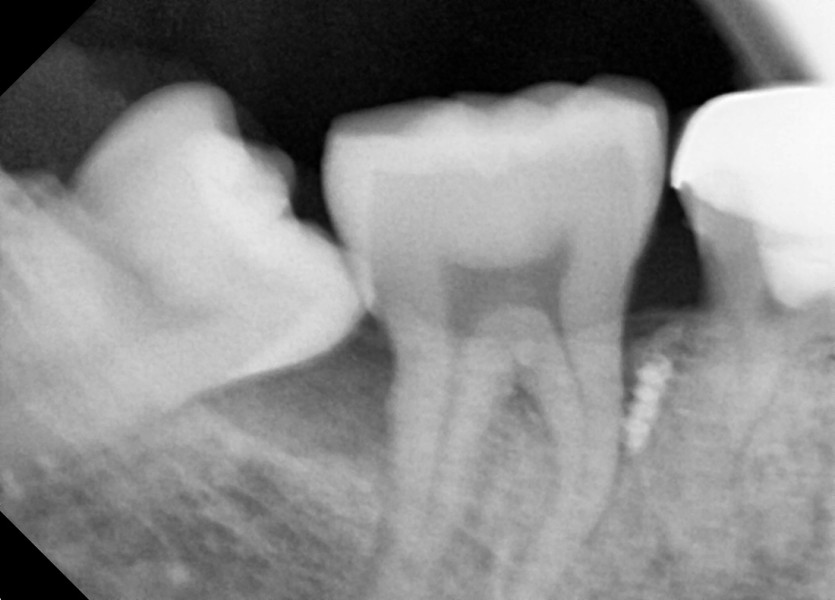

#48 사랑니 발치

구강 외과 전문의가 당일 발치했습니다.